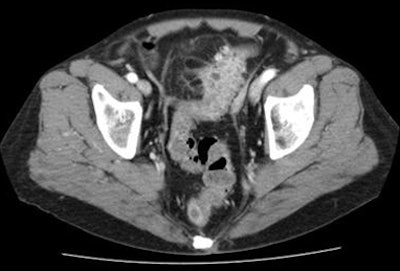

Per the Hinchey method, for example, complicated disease is classified as stage I as long as the complication is local, he said. Once an abscess is found at CT, patients are potential candidates for CT-guided catheter placement under fluoroscopy to drain the abscess.

![]() |

| Diverticular disease above reveals wall thickening and stranding in the pericolonic fatty tissue at CT. Case below shows moderate obstruction and acute inflammation. Both are classified as stage 0 by the Hanson/Stock method and as stage I by the modified Hinchey method. |